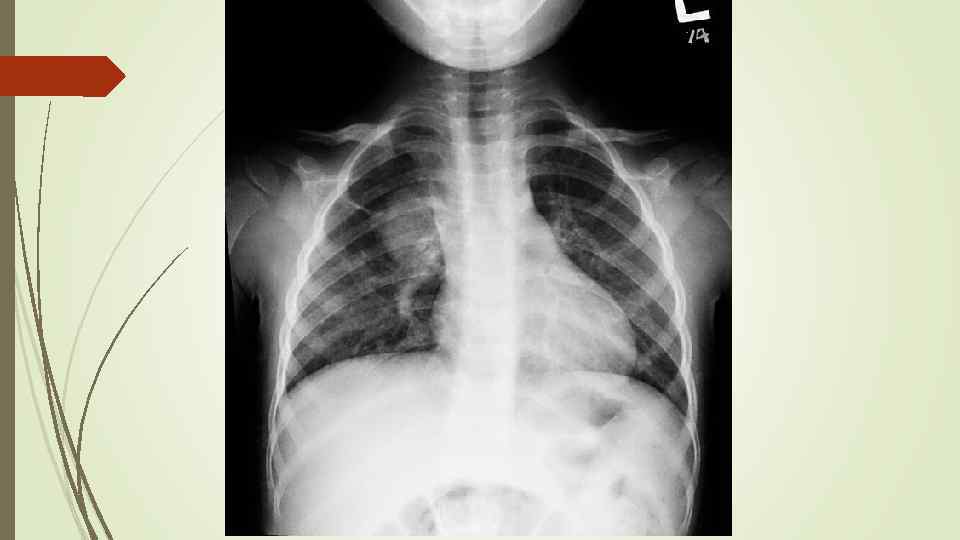

динамика

динамика

Бронхопневмония Характерно наличие двухсторонних множественных очаговых теней. Контуры очагов нечеткие, интенсивность тени небольшая. Инфильтрация неоднородна. Мелкие, малоинтенсивные очаги не всегда выявляются на снимках. Легочный рисунок усилен на всем протяжении легких. Корни расширены, не структурны. Как правило, отмечается реакция плевры, могут быть и экссудативные плевриты.

Бронхопневмония Характерно наличие двухсторонних множественных очаговых теней. Контуры очагов нечеткие, интенсивность тени небольшая. Инфильтрация неоднородна. Мелкие, малоинтенсивные очаги не всегда выявляются на снимках. Легочный рисунок усилен на всем протяжении легких. Корни расширены, не структурны. Как правило, отмечается реакция плевры, могут быть и экссудативные плевриты.